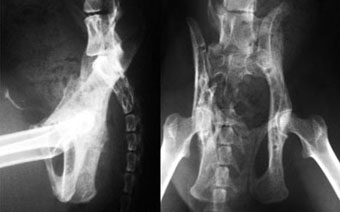

他院からの紹介症例

体重7kg、10か月齢の犬。

腸骨と坐骨の骨折と仙腸関節離断をおこしていました。

腸骨と坐骨はプレート法で整復固定し、仙腸関節離断は創外固定法で整復しました。

写真上段: 手術前

写真下段: 手術後